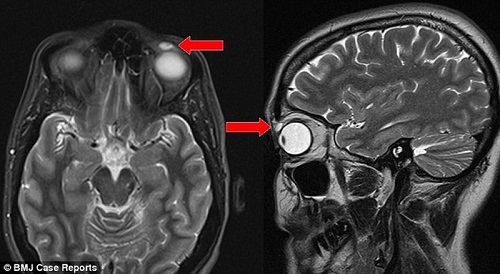

Kết quả chụp cắt lớp vị trí khối u trên mắt người phụ nữ. Ảnh: BMJ Case Reports |

Bằng công nghệ chụp cắt lớp MRI, các bác sỹ nhận thấy có một cục u nhỏ với kích thước 8mm x 4mm x 6mm cho rằng đó là u nang và quyết định lấy bỏ nó ra khỏi mắt bệnh nhân. Nhưng sau khi ca tiểu phẫu hoàn thành, họ mới phát hiện cục u đó thực chất là chiếc kính áp tròng đã rạn vỡ dính vào mí mắt bệnh nhân cách đây 28 năm.